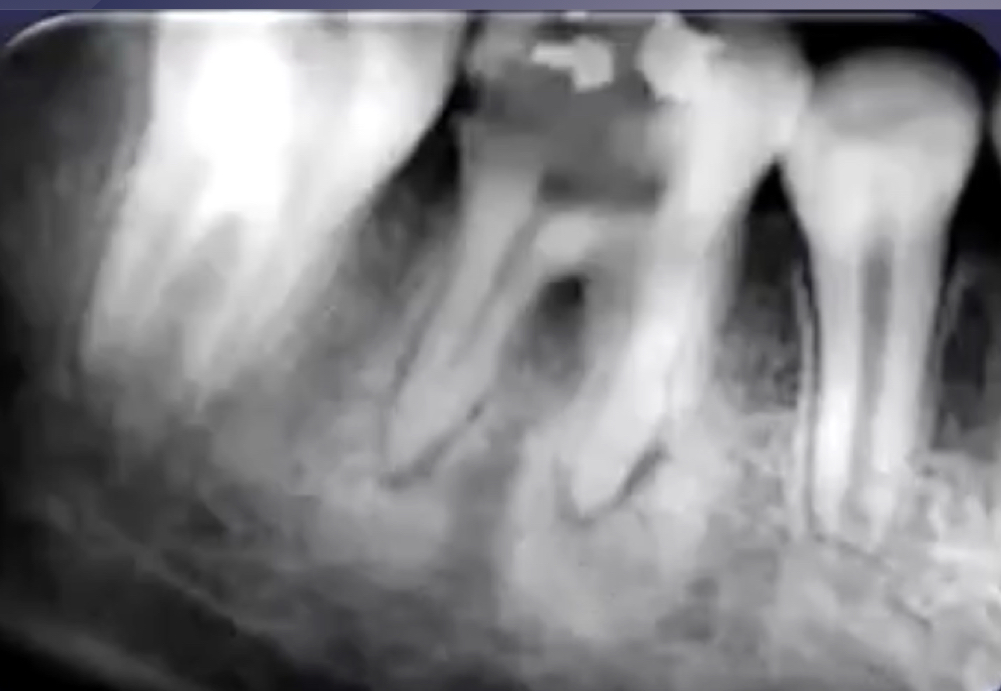

rarefaction

loss of bone mineral

osteitis

bone inflammation

rarefaction + osteitis = ?

increased radiolucency

loss of bone mineral + osteitis = increased radiolucency

rarefying osteitis

rarefying osteitis (LD gone and radiolucency)

chronic inflam with a non-vital toothÂ

radiolucent due to removal of bone

sequelae of acute episodeÂ

includes abscess, granuloma, or radicular cyst (these three have no distinction radiologically)